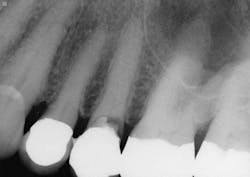

5. All tooth structure gone to the bone. Endodontic treatment. Post and core placed. Not enough tooth structure to provide a ferrule. Nonabusive occlusion (Figures 3 and 4)-Orthodontic tooth extrusion is a technique seldom used in dentistry, but it can possibly save such teeth. In spite of being taught to dental students, I find in my CE courses that orthodontic tooth extrusion is seldom accomplished. If the tooth root is long, the technique can be successful. Additional cost to the patient is necessary, accompanied by the time for orthodontic tooth movement, and a period of bone stabilization before restoring the tooth. Crown lengthening is another option if such treatment will not cause an esthetic challenge. Presence of abusive occlusion adds a strong negative to this clinical situation. Most dentists do not accomplish orthodontic extrusion or bony crown lengthening. Therefore, removal of the tooth and placement of an implant remain as the most predictable and viable solution.